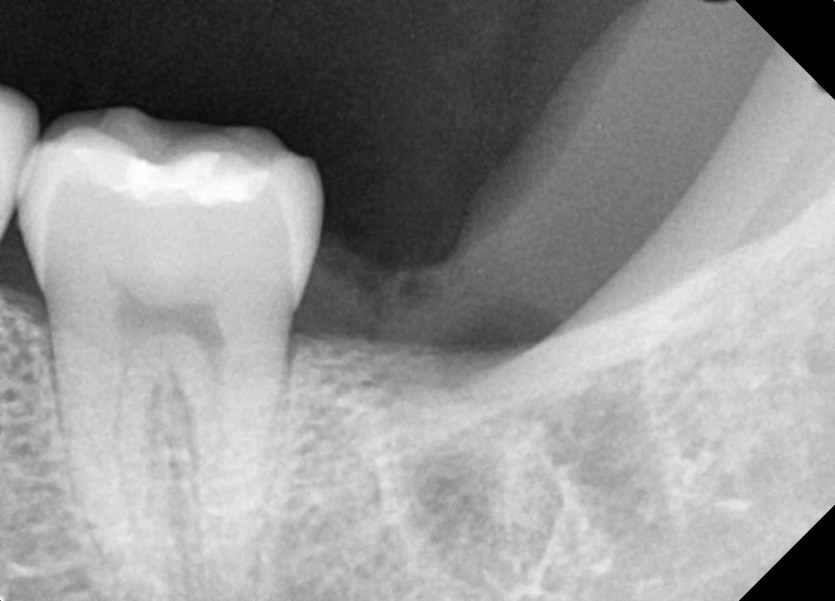

#28,38 사랑니 발치

구강외과 전문의가 당일 발치했습니다.